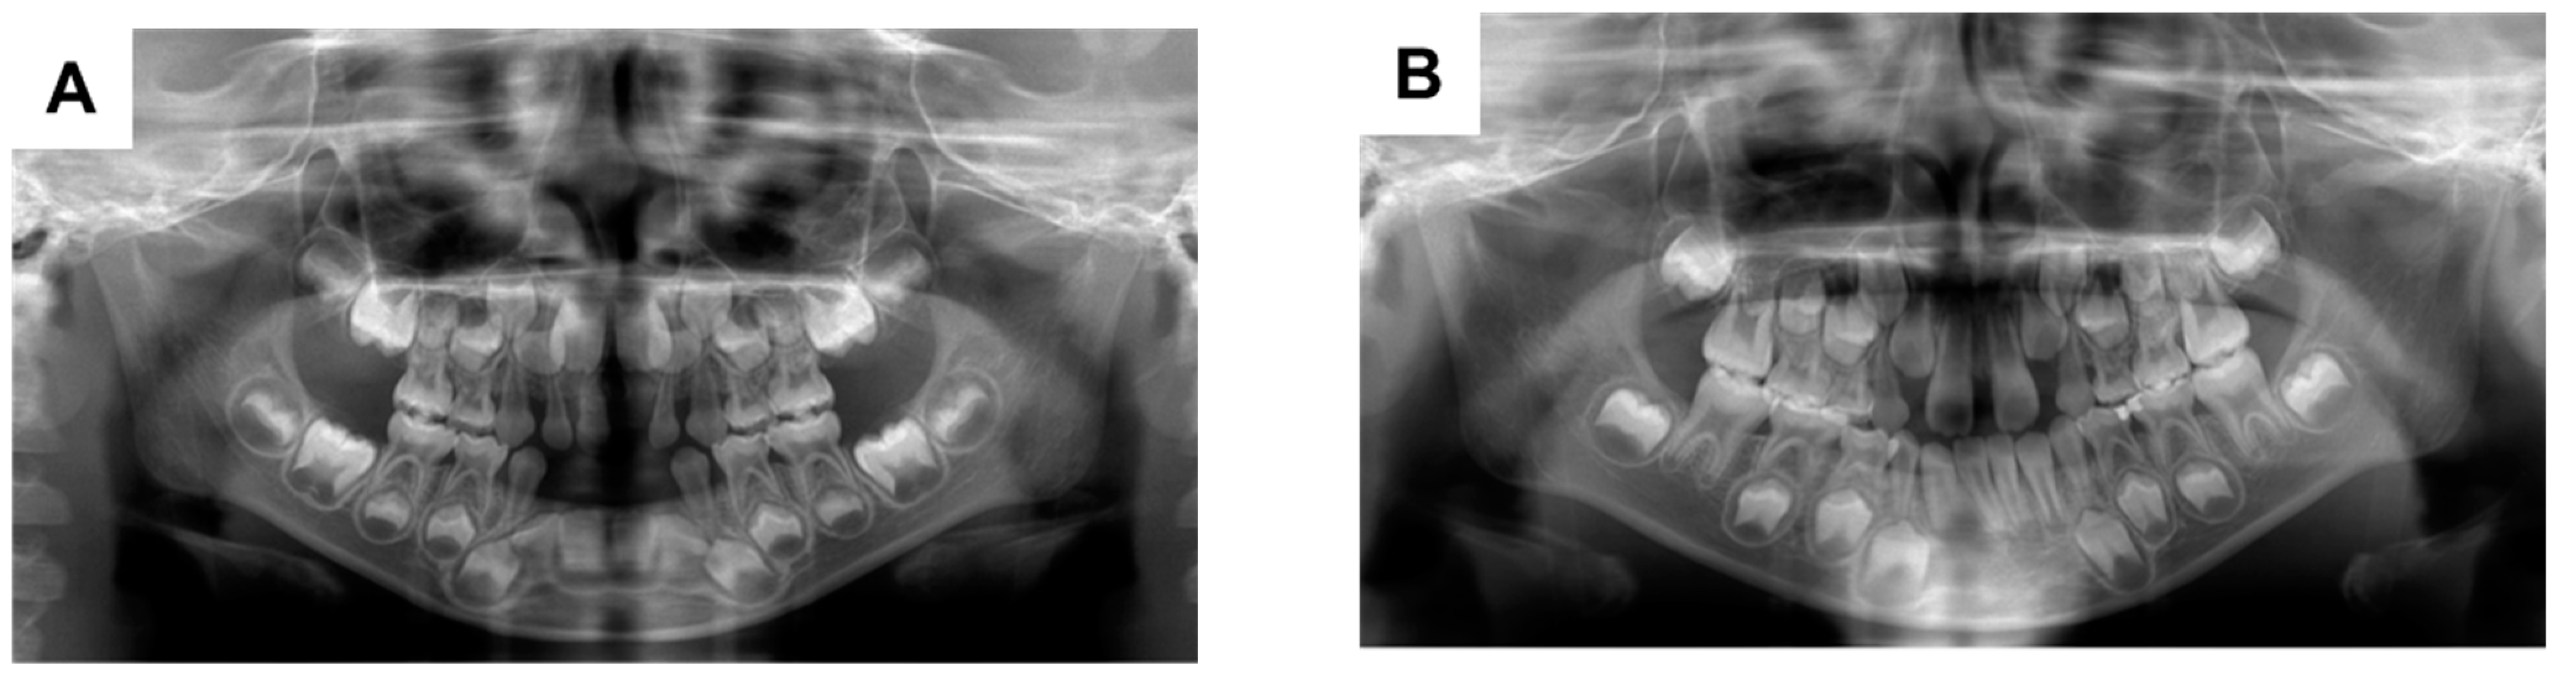

The patient’s primary mandibular right lateral incisor spontaneously exfoliated when he was 2 years and 11 months of age; the primary maxillary left incisor also exfoliated when he was 4 years and 1 month of age. Partial dentures were applied for space maintenance; there were no problems regarding subsequent replacement with the corresponding permanent teeth (Figure 1A). However, the primary mandibular right first molar was appeared to be submerged when the patient was 8 years and 3 months of age; the severity of submergence was greater when the patient was 9 years of age (Figure 1B,C). The primary mandibular right first molar was about 1.5 mm submerged from the primary mandibular right second molar, and the periodontal ligament cavity was partially unclear (Figure 2A,B). The primary mandibular right first molar was considered to be ankylosed, although the corresponding tooth in the opposite quadrant did not show similar findings. Thus, extraction of the affected tooth was performed (Figure 2C). Histopathological analysis of the tooth showed disturbed cementum formation and acellular cementum, with wide and wavy ivory tubules and aplasia (Figure 2D). The patient’s postoperative course was good, and no particular complications were observed. The mandibular right mandibular first premolar showed a tendency to erupt (Figure 1D).

Figure 1. Orthopantomographs taken during follow-up. When the patient was aged (A) 5 years and 10 months; (B) 8 years and 3 months; (C) 9 years; and (D) 10 years and 1 month.